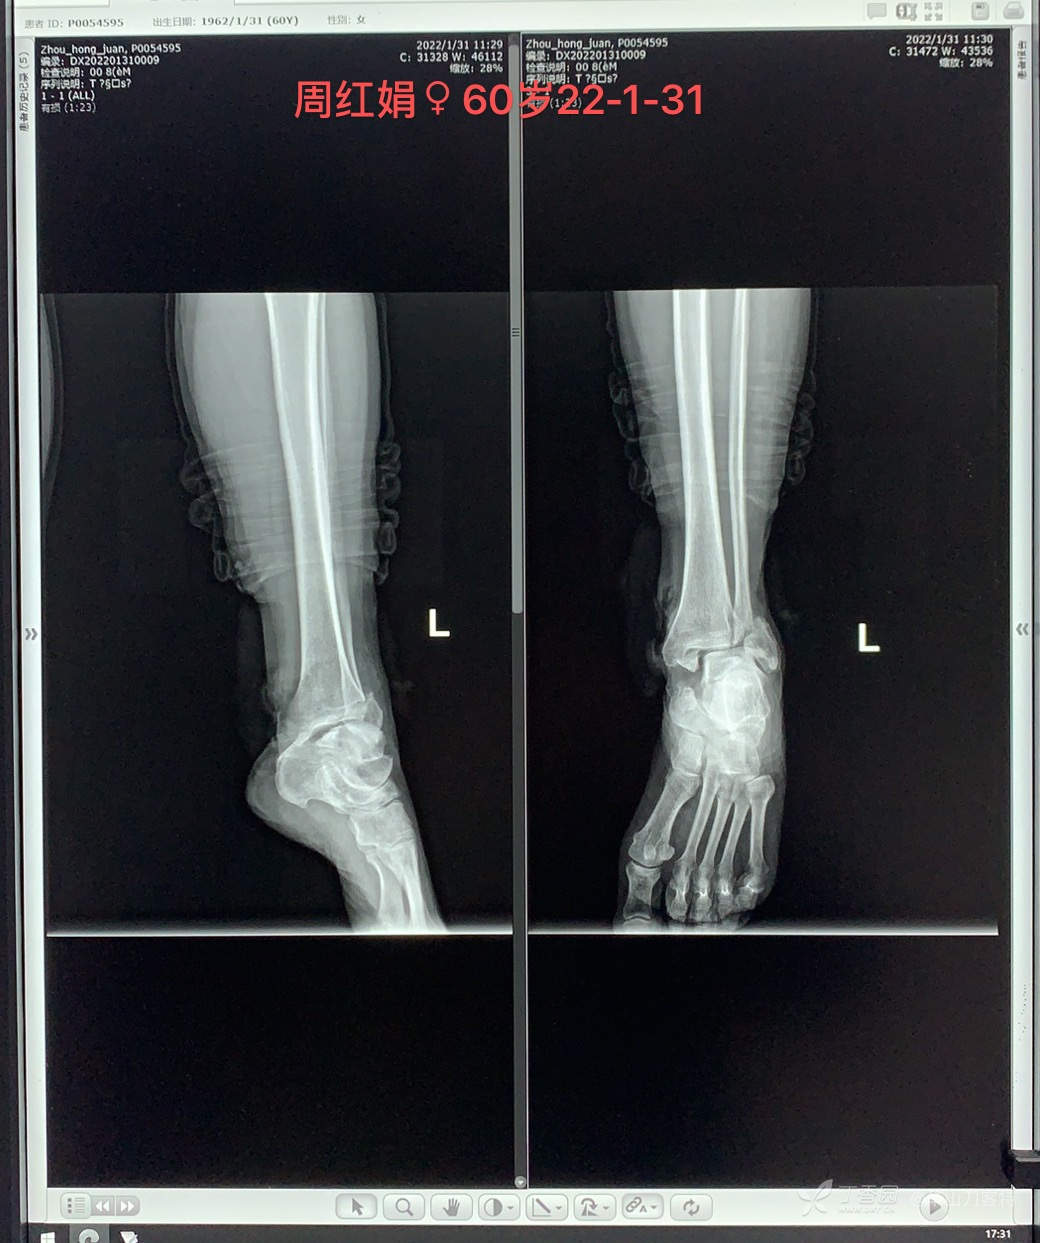

患者,女,60岁,2022-1-31(大年三十)因“交通事故伤及左踝关节流血疼痛一小时”入院。

查体:左踝关节畸形、内踝处开放伤口,末梢血运及感觉正常。

急诊首诊医生予以查体后,行踝关节正侧位片检查,显示:内外踝骨折伴踝关节脱位。摄片过程中患者头晕呕吐(平素晕车),予以加拍头胸腹CT+踝关节CT:除内外踝骨折伴踝关节脱位外未见异常。